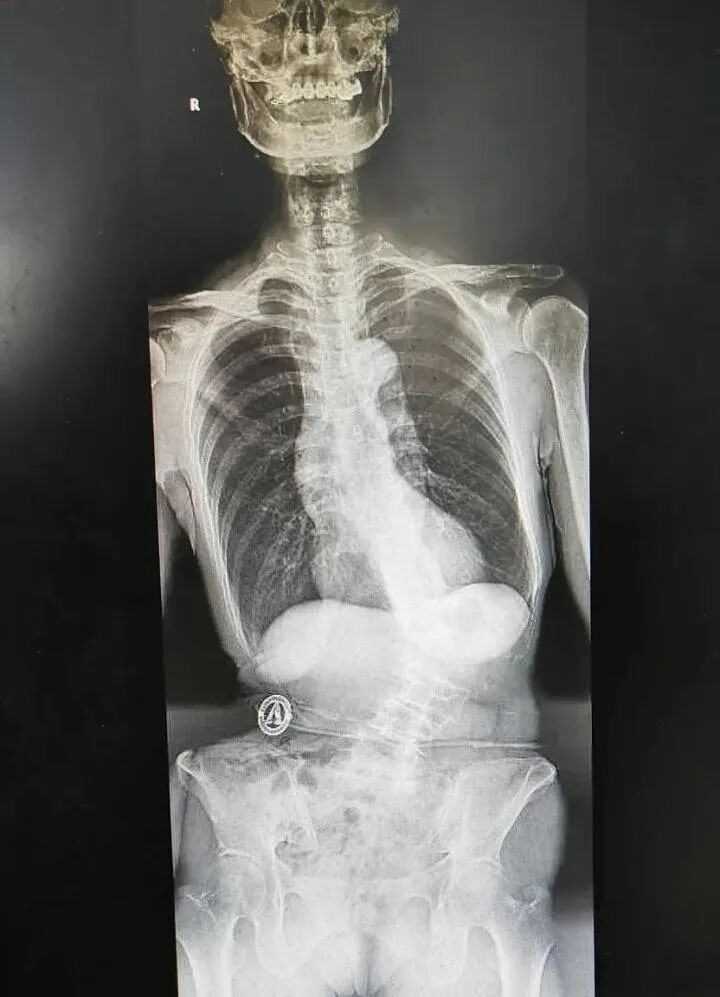

整个人驼得像虾一样

五脏六腑倒向一边

身体里植入十几颗钢钉后

身高“猛长”5厘米